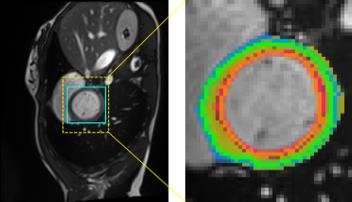

Accurate magnetic resonance imaging (MRI) segmentation is crucial for clinical decision-making, but remains labor-intensive when performed manually. Convolutional neural network (CNN)-based methods can be accurate and efficient, but often generalize poorly to MRI's variable contrast, intensity inhomogeneity, and protocols. Although the transformer-based Segment Anything Model (SAM) has demonstrated remarkable generalizability in natural images, existing adaptations often treat MRI as another imaging modality, overlooking these modality-specific challenges. We present SAMRI, an MRI-specialized SAM trained and validated on 1.1 million labeled MR slices spanning whole-body organs and pathologies. We demonstrate that SAM can be effectively adapted to MRI by simply fine-tuning its mask decoder using a two-stage strategy, reducing training time by 94% and trainable parameters by 96% versus full-model retraining. Across diverse MRI segmentation tasks, SAMRI achieves a mean Dice of 0.87, delivering state-of-the-art accuracy across anatomical regions and robust generalization on unseen structures, particularly small and clinically important structures.